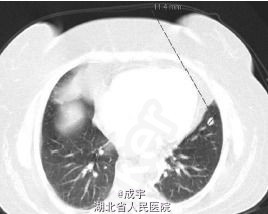

体检:病人呈Cushing’s 综合征表现,满月脸、皮肤毛细血管扩张、皮肤萎缩、水牛背、腹及上肢紫纹、远端肌肉萎缩和外周水肿。血压:158/90mmHg。 辅助检查:检查显示高胆固醇血症、空腹血糖增高、糖化血红蛋白5.2%、低钾,无其它电解质紊乱,无肾功不全。 连续2天尿游离皮质醇明显增高,晨血ACTH和皮质醇明显增高,无ACTH/皮质醇正常昼夜节律,无论是高还是低剂量的地塞米松都不能抑制血和尿中的皮质醇,尿中的5羟吲哚乙酸正常。垂体MRI检查未发现异常,双侧岩下窦标本也未显示中央-外周的ACTH梯度。 CRH刺激试验证实存在异位ACTH存在,胸片、支气管镜及灌洗液细胞学检查无阳性发现,肺CT显示左上肺下舌叶有一12mm的小结节(见图2),腹部CT显示肾上腺及其它腹部器官无异常。